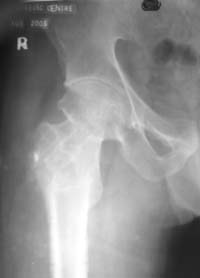

Put attention at the joint condition, please.

And what about pain and function?